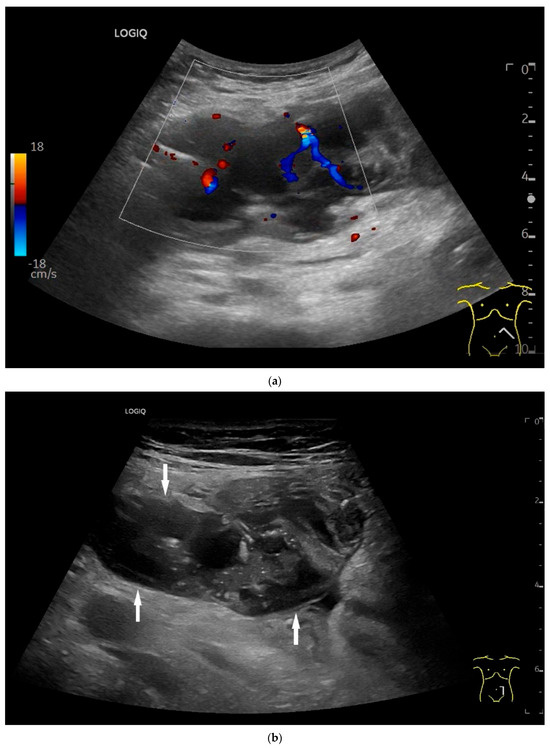

Precise descriptions of subepithelial intramural masses including GIST are known from endoscopic ultrasound (EUS) [128]. Despite the lower resolution and proximity, the findings known from EUS can generally be transferred to US. However, in the small intestine, it is much more difficult to classify the layers, as the healthy wall is only up to 2 mm thick. GIST can develop into the lumen of the gastrointestinal tract or be located extraluminally. On EUS as well as on US, small GIST are generally round, homogeneous, and hypoechoic compared to submucosal layer, but isoechoic to the Lamina muscularis propria. On CDI, they show macrovessels. Larger GIST may be lobulated and heterogeneous, show necroses as hypoechoic or nonechoic liquid areas as well as calcifications. Air inclusions in the tumor are an indication of deep ulceration of the tumor surface with central necrosis and connection to the gastrointestinal tract lumen [55] (Figure 11 and Figure 12).

Figure 11.

GIST. A 30 mm large, very hypoechoic, almost anechoic round mass is visible in the left upper abdomen. This is located in the jejunum; the wall (W) and lumen (L) are visible (a). Macro vessels can be distinguished on Power Doppler, demonstrating that the lesion is solid and not cystic (b). On CEUS with 2.4 mL SonoVue (linear transducer 9 MHz), a small wheel-spoke-like vascular branching is visible at the margin (arrow) (c) with centrifugal enhancement (arrow) (d). Hyperenhancement is heterogeneous in the early arterial phase (e,f) and becomes homogeneous in the later course of the arterial phase (g). The extent of the heterogeneously enhanced tumor is marked with arrows (e). The intensity of the enhancement decreases during the first minute. The tumor is marked with arrows (h). Jejunal segment resection revealed the histology of an epithelioid GIST.

Figure 12.

GIST. Incidental finding of a 35 mm, slightly polycyclic, homogeneous hypoechoic mass in the left upper abdomen (a,b). This changes position with the movements of the small intestine. In CEUS with 1.2 mL SonoVue using the abdominal sector transducer (1–5 MHz), the mass shows homogeneous hyperenhancement in the arterial phase (c). The intensity then decreases (d). The tumor is marked with arrows in CEUS.

In a multicenter study, 98% of GIST of all locations, including the small intestine (no specific location), showed arterial hyperenhancement on contrast enhanced low mechanical index EUS (CELMI-EUS) with SonoVue. Some demonstrated non-enhanced areas as evidence of necrosis [55].